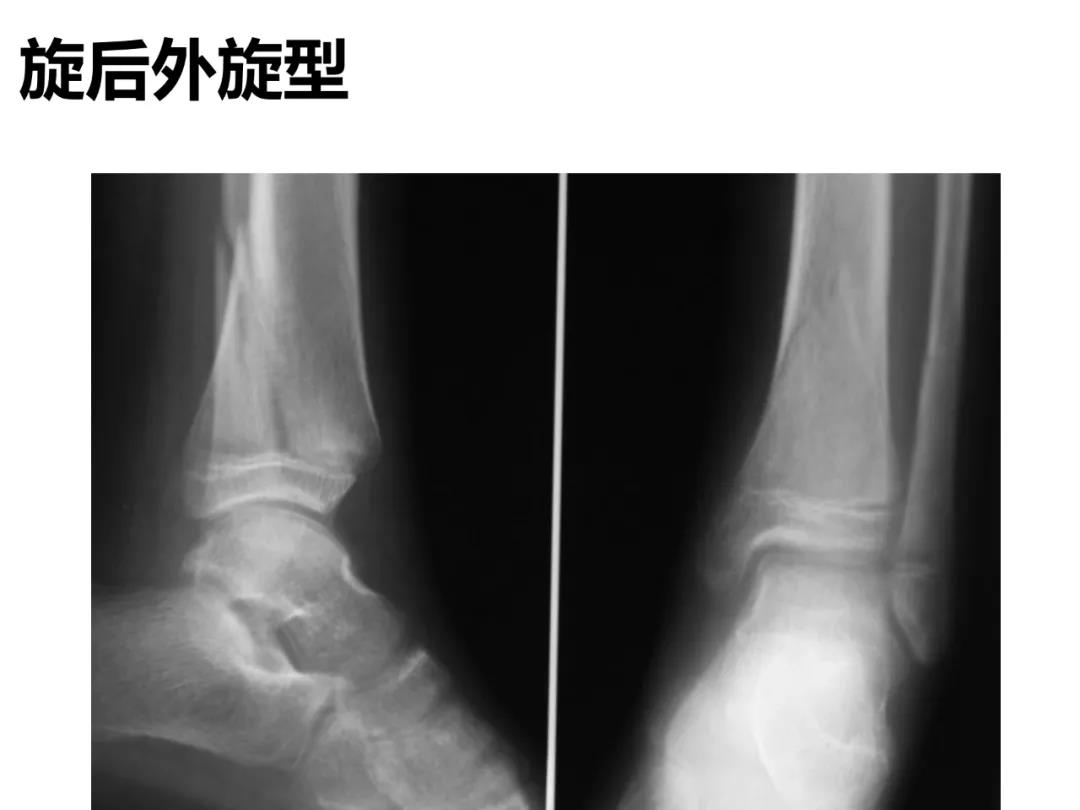

小儿骨科X线片汇总,临床读片宝典!